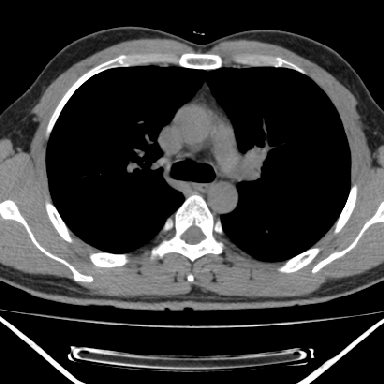

右上后纵隔脊柱旁类圆形肿块,边界光整,与胸腔呈钝角,首先考虑来源于肺外,神经源性肿瘤(神经鞘瘤可能大,神经鞘瘤)

病灶与椎间孔间存在脂间隙,病灶较大,椎间无明显异常改变,与胸膜移行处可见尾状影,考虑胸膜肿瘤,以良性间皮瘤可能性大

病灶最大径线处于肋间隙,不排除起源于肋神经源性肿瘤

右上后纵隔脊柱旁类圆形肿块,边界光整,与胸腔呈钝角,首先考虑来源于纵膈,神经源性肿瘤可能大。

右上后纵隔脊柱旁见长椭圆形肿块,边界光整,与胸壁呈钝角。周围骨质未见异常。

考虑、1、后纵隔神经源性肿瘤;

2、不除外单发胸膜间皮瘤。